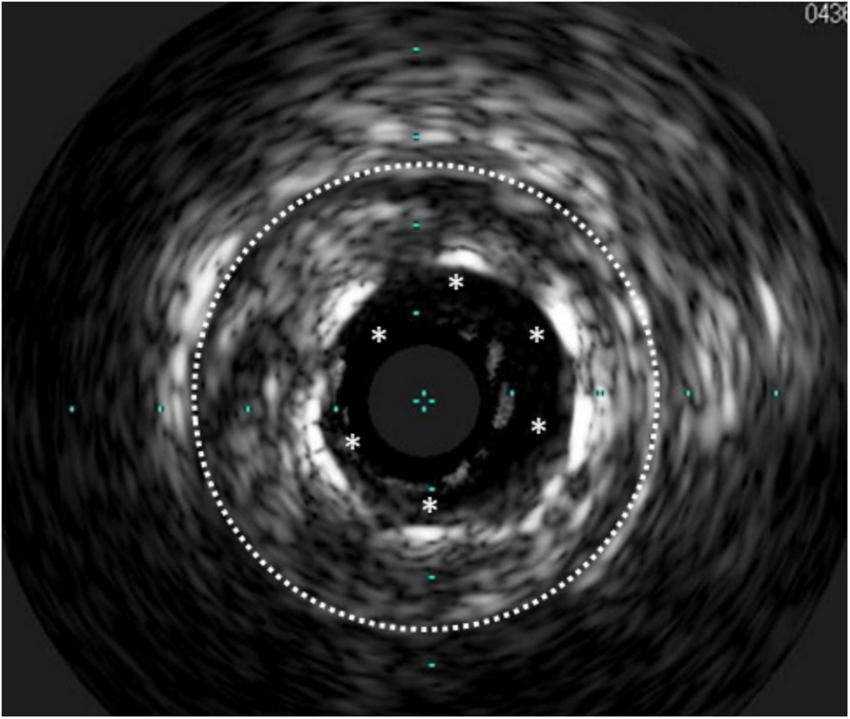

FIGURE 3

Calcific lesions at intravascular ultrasound (Left) and optical coherence tomography (Right). The limitation of IVUS in this case is that the lesion projects a shadow that does not allow measuring its depth.

FIGURE 4

Cracks in the subintimal calcium after coronary lithotripsy.

While it is difficult to evaluate calcium thickness or area with IVUS because its surface reflects ultrasound waves almost entirely, OCT can penetrate through calcium, so that its thickness and area can be evaluated (Figure 3). This was shown to be relevant, although to a lesser degree than the arc of calcium, so that it affects the minimal stent diameter achieved (58). In another study, a thinner calcium thickness after rotational atherectomy (optimal threshold was 0.67 mm) predicted the formation of cracks after balloon angioplasty which in turn permitted a larger lumen gain and a greater stent cross-sectional area (59). An OCT-based calcium scoring system has been proposed, whereby a maximum angle of calcium >180°, together with a maximal thickness >0.5 mm, and length >5 mm, predicted stent underexpansion (based on the smallest stent area divided by the average of proximal and distal reference luminal areas) with a slightly better ability than the angiographic detection of severe calcium (60). On the other hand, it has been demonstrated that the detection of calcium fractures by OCT (Figure 4) confirms adequate modification of heavily calcified culprit lesions before stenting and resulted in a greater MSA, and stent expansion immediately post-PCI, as well as smaller percent diameter stenosis, less frequent binary restenosis, and less ischemic-driven TLR, at 10-month follow-up (61).